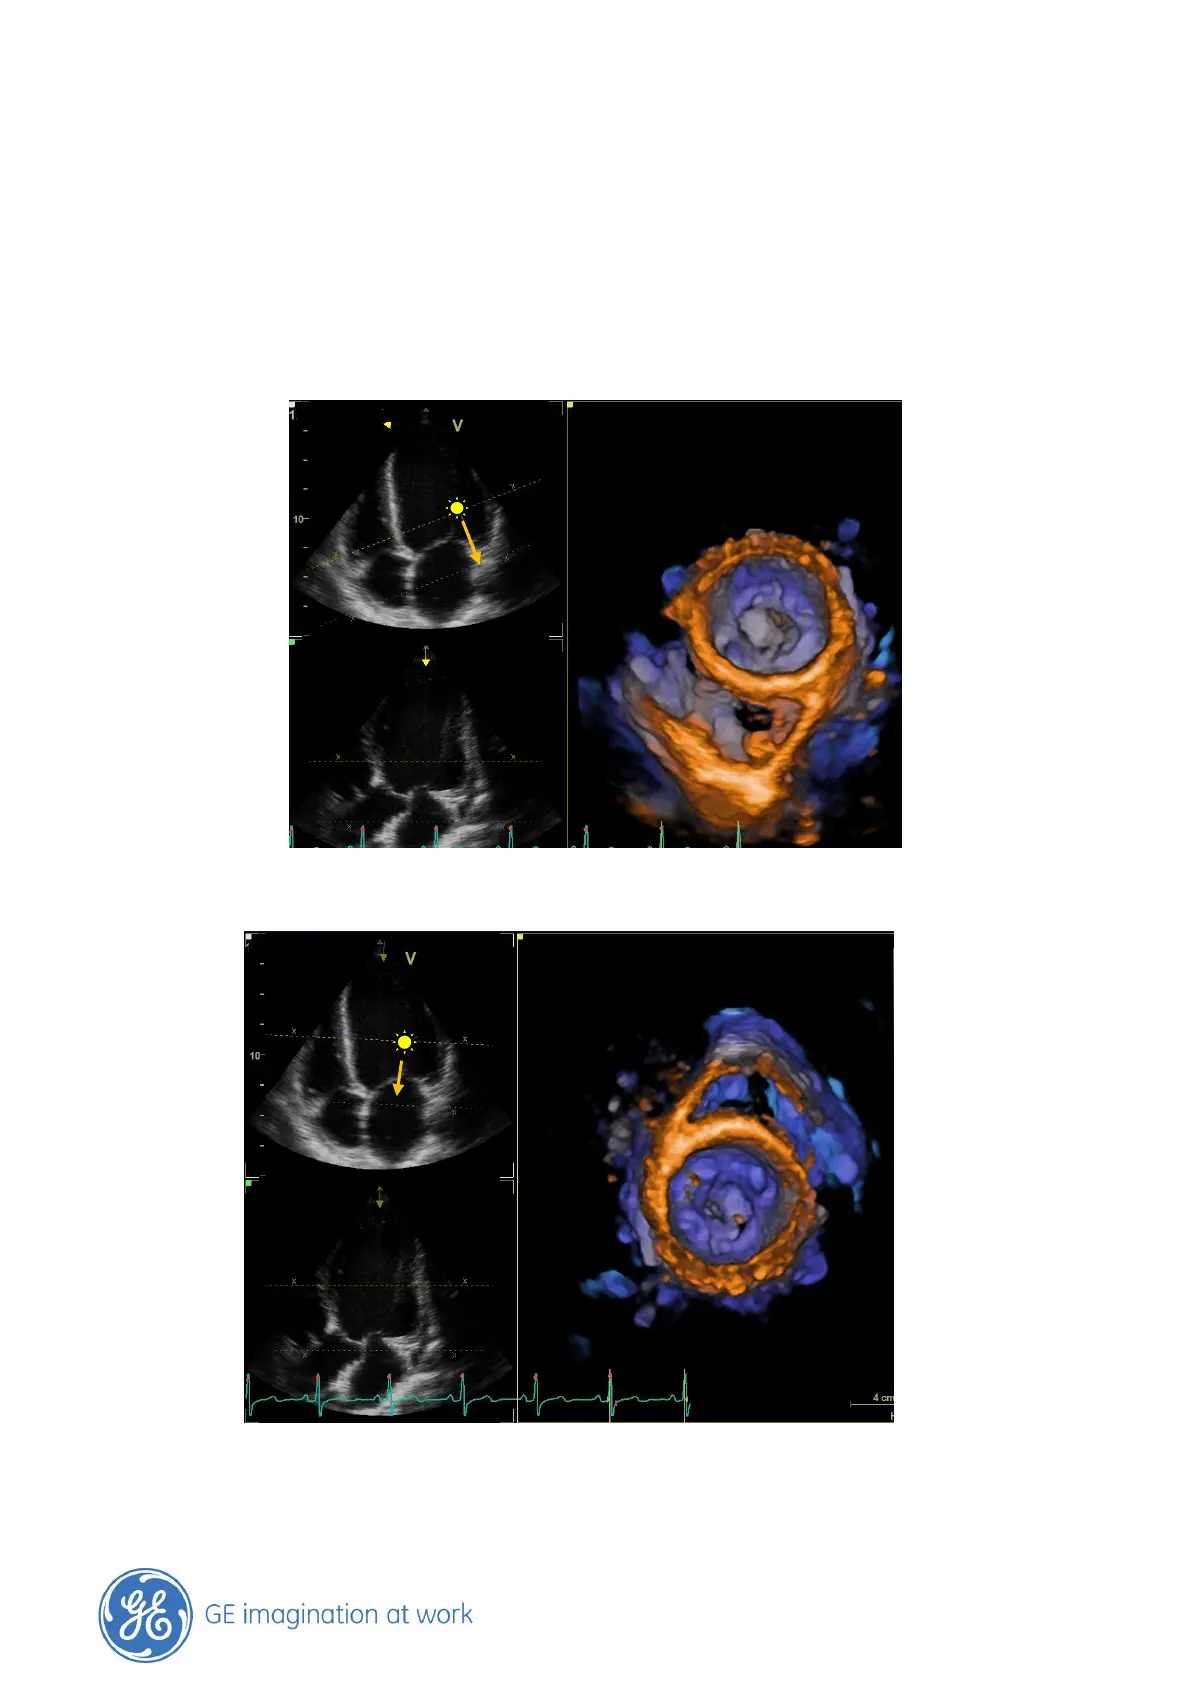

While moving the cursor the system immediately shows you the result in the rendered image.

As long as the end point is not set, the cursor can be adjusted in all directions and the rendered

image will visualize the cropped area. In this way you can map through the structures to find the

best position.

Adjust the cursor to visualize the structure you want to see